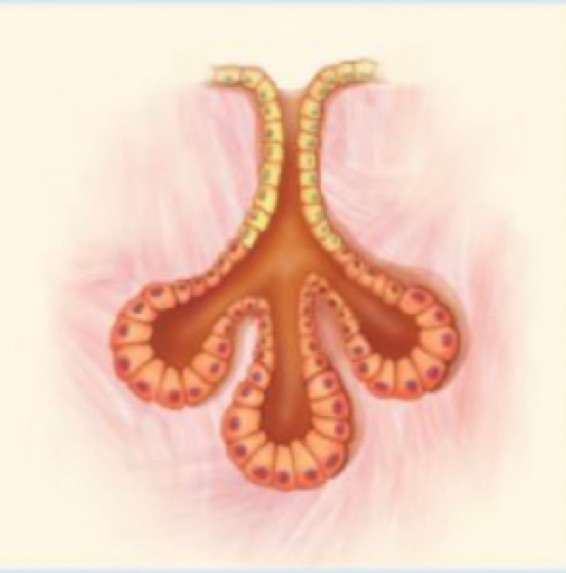

1 Tissue ประเภทใด

5 จากภาพเป็นเนื้อเยื่อชนิดใด

6 จงบอกชนิดของเนื้อเยื่อ

12 จากภาพคือ เนื้อเยื่อชนิดใด

13 จากภาพ คือเนื้อเยื่อใด